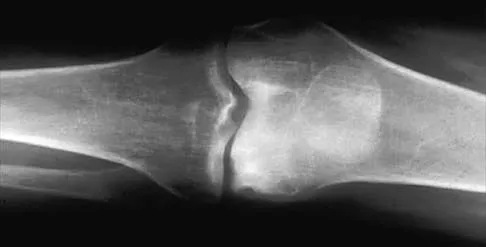

What is the most common reason for reoperation in total knee arthroplasty?

Explanation